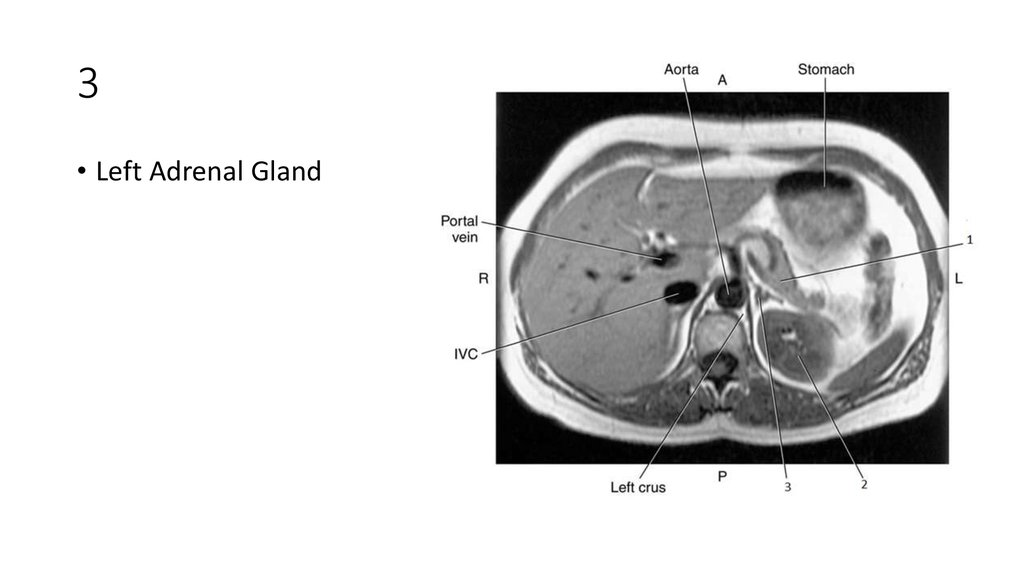

• Left Kidney

48. 3

49. 3

• Left Adrenal Gland